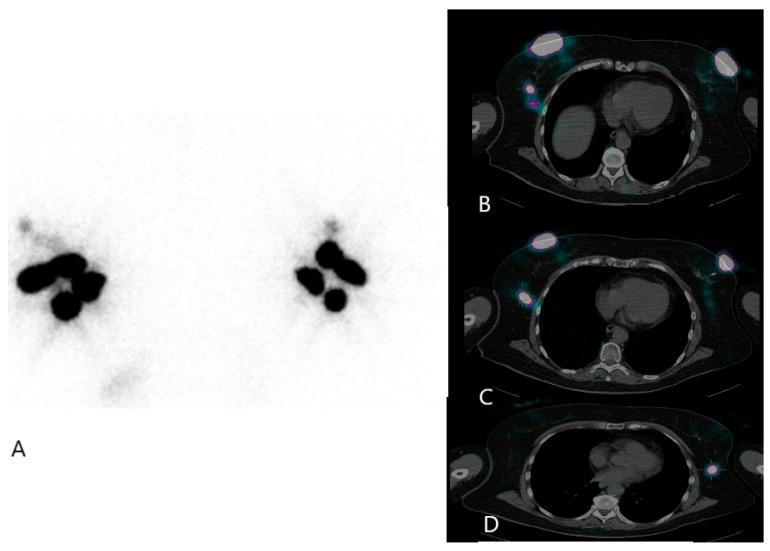

Breast cancer stands out as the most commonly diagnosed cancer among women globally. Precise lymph node staging holds critical significance for both predicting outcomes in early-stage disease and formulating effective treatment strategies to control regional disease progression in breast cancer patients. No imaging technique possesses sufficient accuracy to identify lymph node metastases in the early stages (I or II) of primary breast cancer. However, the sentinel node procedure emerges as a valuable approach for identifying metastatic axillary nodes. The sentinel lymph node is the hypothetical first lymph node or group of nodes draining a cancer. In case of established cancerous dissemination, it is postulated that the sentinel lymph nodes are the target organs primarily reached by metastasizing cancer cells from the tumor. The utilization of the sentinel node technique has brought about changes in the assessment of lymph nodes. It involves evaluating the sentinel node during surgery, enabling prompt lymph node dissection when the sentinel node procedure is positive. Additionally, histological ultra-stratification is employed to uncover occult metastases. This review aims to provide an update of this valuable technique, with focus on the practical aspects of the procedure and the different histological protocols of sentinel node evaluation in breast cancer.